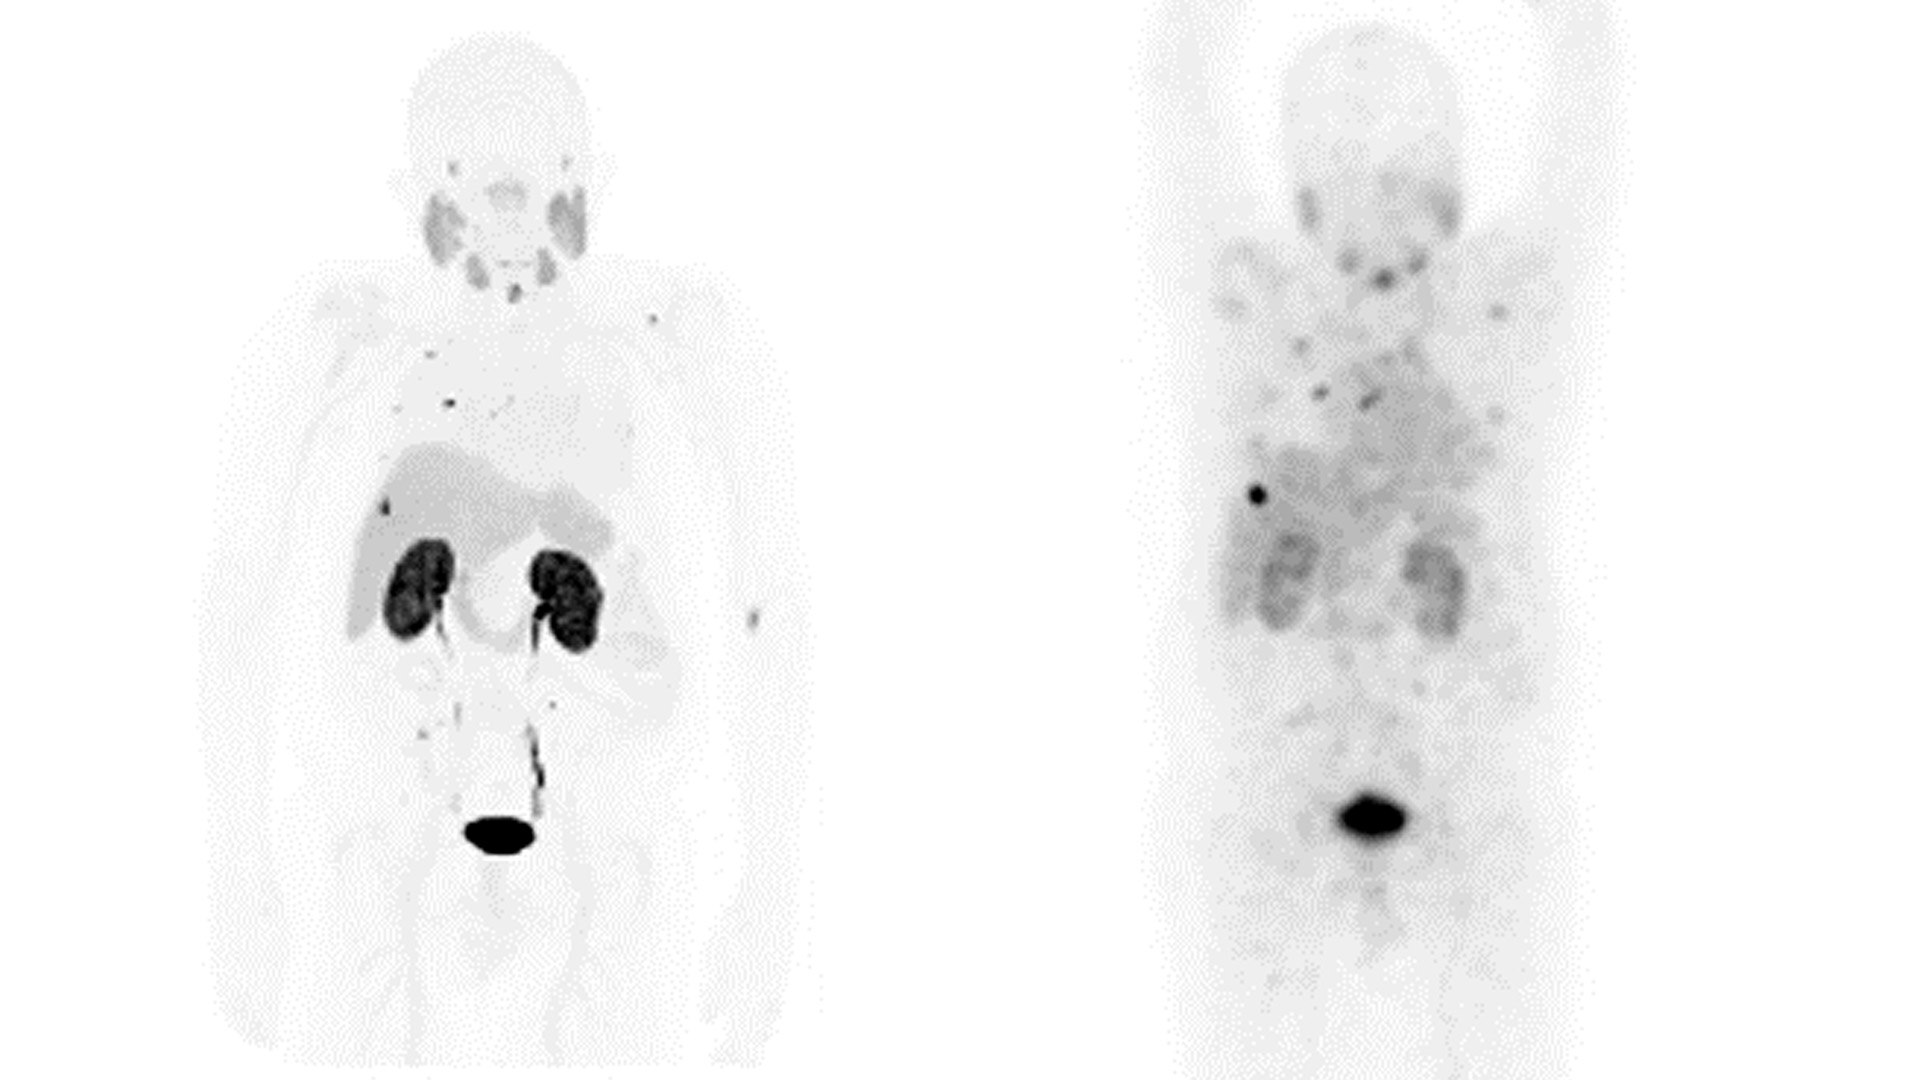

THERAPY IMAGING AND MONITORING

GE Healthcare is shaping the future of Theranostics today with precise imaging and monitoring solutions and innovations of treatment response.